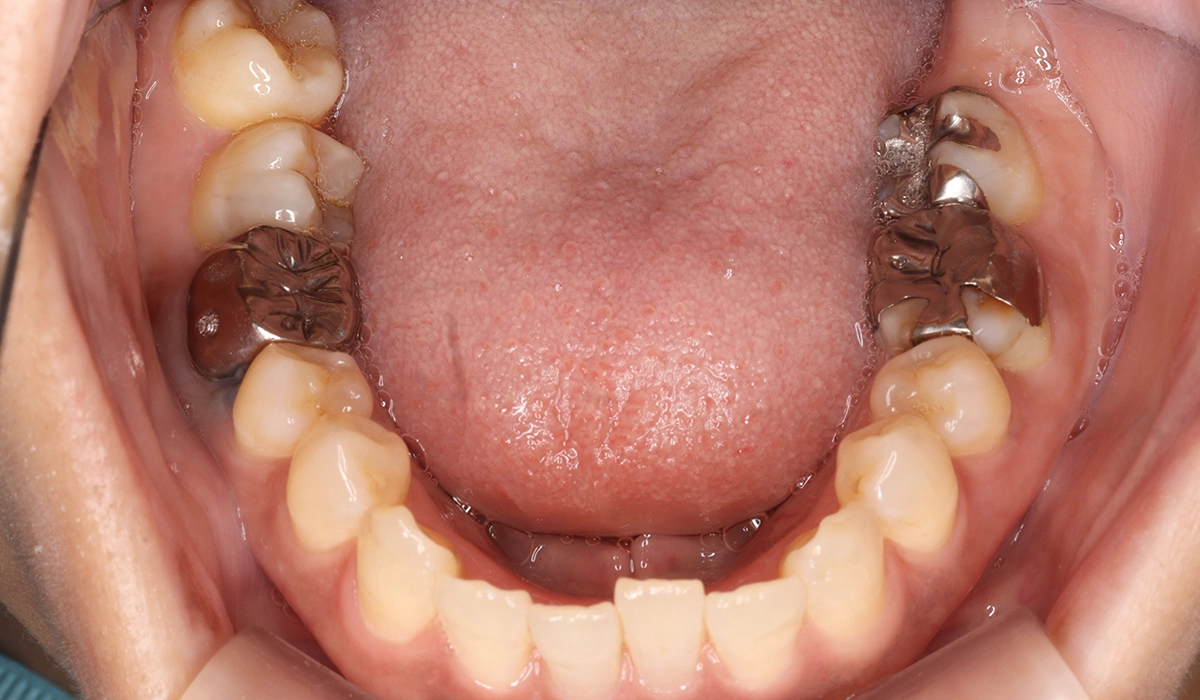

術前:下顎